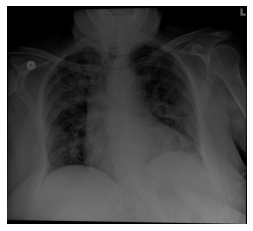

Figure 3 illustrates the frameworks for each of the prediction tasks over the succeeding 24 hours. Figure 3(a) shows an example of SIP predictions from a patient with increased lung opacity. In this case the patient did not suffer any adverse event in the next 24 hours, but ultimately suffered all three adverse events within 72 hours. Figure 3(b) shows an example of ORP predictions from a patient that required increased oxygeen within 24 hours. In Figure 3(c), a sequence of chest X-rays with increasing lung opacity is used by the MIP model to predict COVID deterioration for a patient. The images were taken 49 hours apart. For the case of Figure 3(c), the patient was transferred to the ICU, intubated, and suffered a mortality within 24 hours.

Refer to caption SIP Predictions ICU24: 0.844 Int24: 0.997 Mor24: 0.559

(a)

Figure 3: Example model outputs for ICU (ICU24), intubation (Int24) mortality (Mor24), and oxygen greater than 6 L per day (>6L24) prediction tasks, all at 24 hours. (3(a)) Example SIP outputs based on a single image with evident increased lung opacity. In this case the patient did not suffer any adverse event in the next 24 hours, but would ultimately suffer all three adverse events within 72 hours. (3(b)) Example ORP output based on a single image. This patient required greater than 6 L per day of oxygen within 24 hours. (3(c)) Example MIP outputs. Both images were taken from the same patient with 49 hours of separation. Increased lung opacity is observable in the second (later) image. The patient suffered all three adverse events within 24 hours.